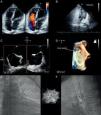

On transthoracic echocardiography no residual shunt was observed but the device was not identifiable (Figure 1A); after injection of agitated saline solution in a vein of the right arm and the Valsalva maneuver, a remarkable paradoxical right-to-left shunt appeared (Figure 1B, video clip 1). The estimated systolic artery pressure was 25mmHg.

To better understand the pathophysiology of the shunt 3D real-time transesophageal echocardiography was performed. The septal occluder was not found on the interatrial septum (Figure 1C). A small interatrial defect was identified close to the foramen ovale (Figure 1D, video clip 2) with a trivial left-to-right shunt (Qp/Qs 1.1) in baseline conditions; the agitated saline contrast test after the Valsalva maneuver was markedly positive. Given the suspicion of distal embolization of the device, cardioscopy was performed: the Biostar was found in the left pulmonary artery (Figure 1E and F, video clips 3 and 4), without hemodynamic effects (mean pulmonary artery pressure 18mmHg).